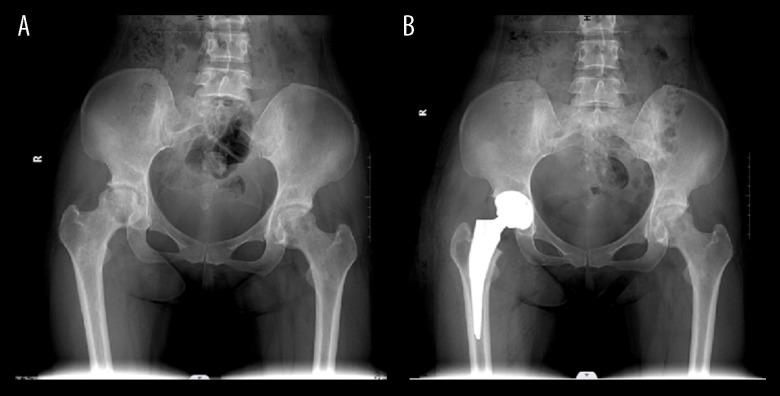

BACKGROUND This retrospective study from a single center aimed to compare outcomes following total hip arthroplasty (THA) in 302 patients diagnosed with Association Research Circulation Osseous (ARCO) stage III and stage IV osteonecrosis of the femoral head (ONFH). MATERIAL AND METHODS The study included 302 patients who underwent THA for ONFH between January 2018 and September 2021. Patient groups included ARCO stage III (n=145) and ARCO stage IV (n=157). Outcomes measured included duration of disease, operative time, intraoperative blood volume, postoperative length of hospital stay, pain measured by the visual analog scale (VAS) score, Harris hip score (HHS), and forgotten joint score (FJS). RESULTS Patients with ARCO stage III ONFH had a significantly shorter operative time (P=0.009), shorter length of hospital stay (P=0.021), and reduced volume of intraoperative bleeding (P=0.021) compared with patients with ARCO stage IV ONFH. There were no significant differences in disease duration (P=0.310), postoperative complications (P=0.07), preoperative (P=0.086, P=0.156) and postoperative (P=0.062, P=0.173) HHS and VAS scores, respectively. Patients with stage III ONFH reported significantly higher FJS scores at 3 months, 6 months, and 1 year after THA. CONCLUSIONS Patients who underwent hip arthroplasty for ARCO stage III femoral head necrosis experienced shorter operative time and hospital stay, less intraoperative bleeding, and better restoration of hip function than those with ARCO stage IV. Moreover, stage III patients were more prone to "forget" their hip arthroplasty experience within 1 year of surgery.

该研究纳入了 2018 年 1 月至 2021 年 9 月期间因 ONFH 接受 THA 的 302 例患者。患者分为 ARCO Ⅲ期(n=145)和 ARCO Ⅳ期(n=157)。测量的结果包括疾病持续时间、手术时间、术中失血量、术后住院时间、视觉模拟评分(VAS)评分、Harris 髋关节评分(HHS)和遗忘关节评分(FJS)测量的疼痛程度。